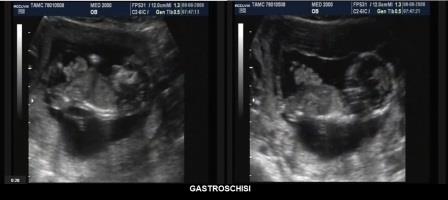

GASTROSCHISI

La gastroschisi è una malformazione congenita caratterizzata da erniazione dei visceri attraverso un difetto della parete addominale presente sul lato destro non ricoperto da membrana, adiacente a un cordone ombelicale intatto (Castilla EE, 2008).

Diagnosi ecografica

La diagnosi ecografica si basa su due

aspetti caratteristici: la visualizzazione di anse intestinali liberamente

fluttuanti nel liquido amniotico e la localizzazione del difetto a destra della

normale inserzione del cordone ombelicale. Il difetto è in genere di piccole

dimensioni (inferiore a 2 cm.) comparato al volume di intestino erniato.